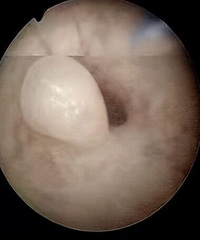

50% 孕妈遭遇过的难关,诊疗切勿遗漏这个细节

1个月前 收录

阅读:2931回复:2